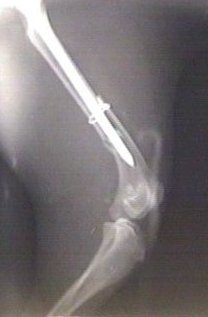

Røntgenmyndir av brotnum lærleggi hjá hundi. Á seinnu myndini er lærleggurin settur saman aftur og seymur settur gjøgnum mergin.